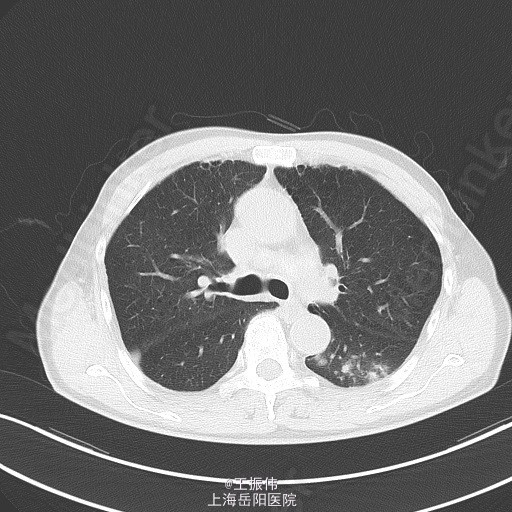

主诉、病史:老年男性,咳嗽咳痰15天,患者15日前因受凉后出现咳嗽,咳黄脓痰,自觉有发热,未测体温,6月25日至我院查血常规:白细胞:7.7*10^9/L,血红蛋白:106g/L,血小板:149*10^9/L,中性粒细胞:68.7,胸部CT:右肺上叶占位灶,两肺小结节灶,纵膈淋巴结增大,左肺下叶、右肺中叶炎症;两肺气肿伴肺大泡。自服止咳中成药(具体不详)后无明显好转。6月27日至地段医院就诊,予头孢羟氨苄片、金荞麦片、强力枇杷露,未见明显好转。

气管居中,颈静脉正常,胸廓两侧对称,无桶状胸,呼吸运动两侧对称,呼吸频率20次/分,肋间隙正常,无胸膜摩擦感。两肺叩诊清音,右肺可闻及湿性啰音,胸部CT:右肺上叶占位灶,两肺小结节灶,纵膈淋巴结增大,左肺下叶、右肺中叶炎症;两肺气肿伴肺大泡。组织病理【z155818】:灰白组织2粒,直径0.1cm。诊断:(左肺下叶开口)肉芽肿性炎,结核可能,请临床做相关病原体检测。支气管镜痰涂片:找到抗酸杆菌。